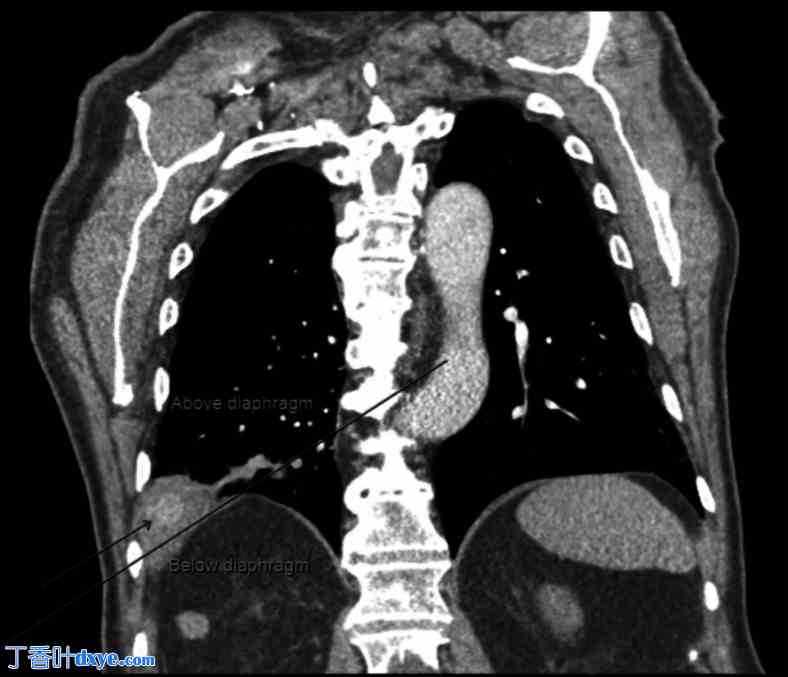

患者入院时血流动力学稳定。全血细胞计数未见白细胞增多,白细胞计数为1.02万/μL(4-1.1万/μL)。血红蛋白和血细胞比容与前一天相比保持稳定,分别为13.5 g/dL(13-17.7 g/dL)和41.9%。检查时,患者维持……。胸部增强CT扫描显示,腹部内有一复杂肿块,位于肝脏VII段附近,可能通过右半膈肌侵蚀至胸腔(图1)。右下肺叶邻近致密实变,累及外侧和后基底节段,肺动脉相应分支闭塞,中心有一2厘米高密度影。此外,还观察到一个大的右肺门淋巴结,被描述为恶性或反应性。

图1.

胸部CT扫描显示病变如黑色箭头所示,长线切开膈肌平面。